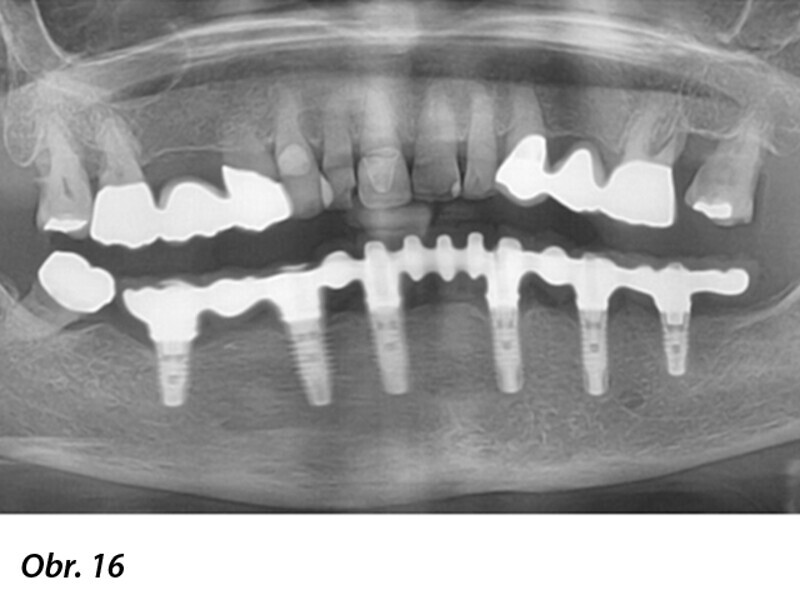

Počítačem asistované, šablonou se řídící okamžité zavedení a zatížení implantátu v dolní čelisti